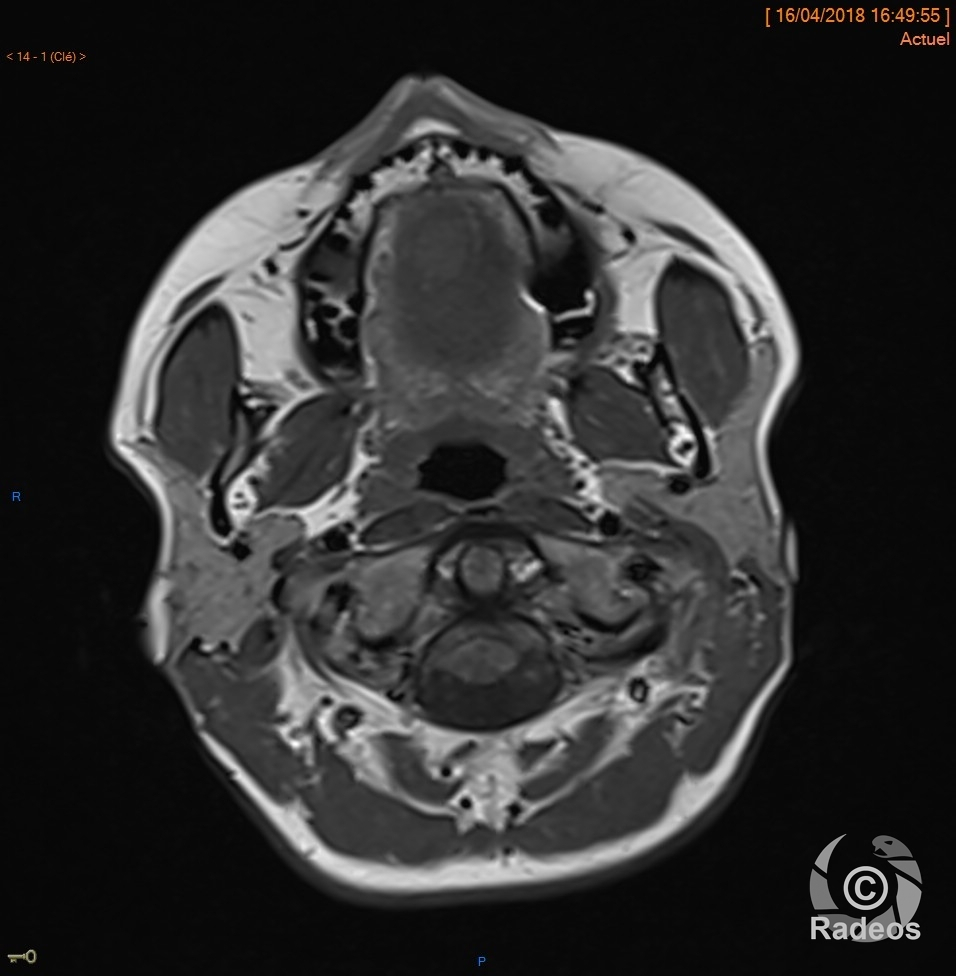

Aspect IRM d'une fibromatose profonde de la paroi abdominale. Découverte fortuite d'un angiome hépatique gauche.

Fibromatose profonde de type desmoïde